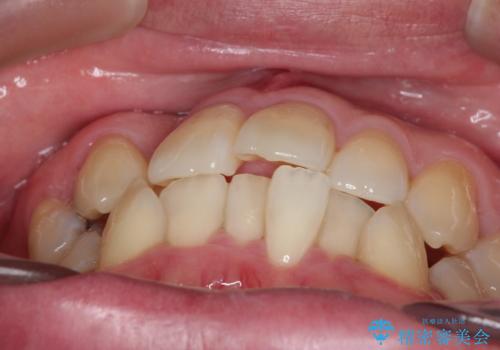

- 「歯のデコボコと前歯が引っ込んでいるのを治したい」を主訴に来院された患者様です。

正面から見たときに右上2が全く見えないくらい、右上2が後ろに引っ込んでいる状態でしたが綺麗に並べる事が出来ました。